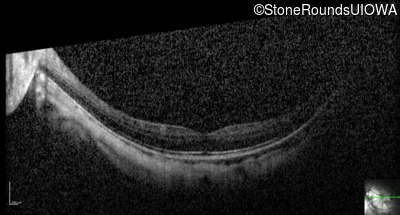

Optical Coherence Tomography - Left - 20/25 -2

Exemplar / OCT Stack

OCT Stack